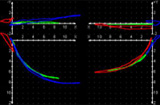

4.アキシオグラフ

顎の運動や噛みあわせを検査

- 事前に歯ぎしりや食いしばりなどの歯にかかる力を検証し、咬合器で噛み合わせ・顎の動き・歪みを検査します。